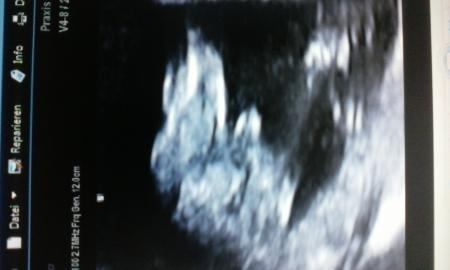

Hi ihr lieben....hab heute bei 15+2 dieses Bild bekommen. ...was meint ihr....blau oder rosa einkaufen?

Also das rechts und ganz links sind die Beinchen-Bild ist leider hochkant deshalb schwierig, bekomme es nicht richtig rum geladen....na ja und in der Mitte zwischen den Beinchen.....Arzt sagt 100% Junge. ...will mal andere hören. ....zum Vergleichen. Liebe Grüße!

Junge eindeutig für mich!!! Sah bei meinen auch immer so aus! Und ja immer so früh, meine Ärztin würde nix sagen wenn sie sich nicht sicher ist

Auf deinem erkenn ich nur einen Hasen... Der Arzt hatte es beim US gezeigt, das waren ja bewegliche Bilder. Darauf konnte man es gut sehen.

Eindeutig Junge! Das Bild ist von unten,genau zwischen den Beinchen geschallt.

Ich würde auf einen aufrecht stehenden Jungen tippen ;) Aber in der 15. SSW ist es noch etwas früh. Am Anfang sieht es bei Mädchen ja was ich gelesen hab auch nach einem kleinen Penis aus und bildet sich erst dann zurück. Wobei das jetzt nicht so klein aussieht... Aber vielleicht ist es auch nur eine blöde Perspektive und es ist sonst was. Also verlassen würde ich mich so früh da noch nicht drauf. LG Lilly

Ne,ne… das ist mehr als eindeutig und da wird sich nichts mehr zurück bilden. Habe beruflich auch damit zu tun.